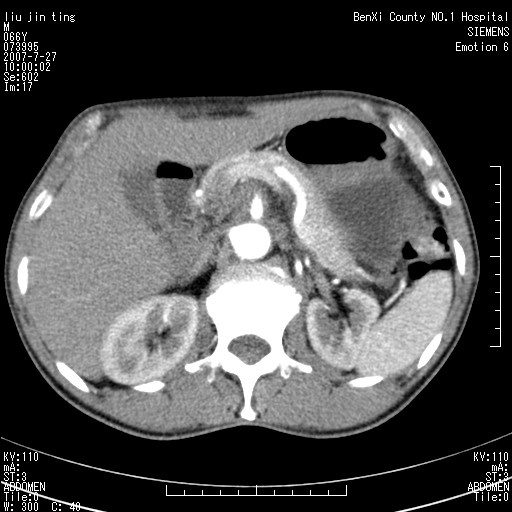

腹痛,背痛,无恶心呕吐,不黄,彩超示胰腺钩癌,ct扫描病灶平扫30-40hu,增强后动脉期40--60hu,静脉期50-68hu,真的是钩突上的么?您要试一试么?

动脉期

沿着肠系膜上动脉呈匍匐性生长的软组织肿块,形态不规则,包绕肠系膜上动脉,呈明显强化,考虑来源于肠系膜的恶性肿瘤

沿着肠系膜上动脉呈匍匐性生长的软组织肿块,形态不规则,包绕肠系膜上动脉,呈轻-中度强化,考虑来源于肠系膜的恶性肿瘤。

钩突是正常的,只见腹膜后淋巴结的肿大,考虑淋巴瘤或转移可能。